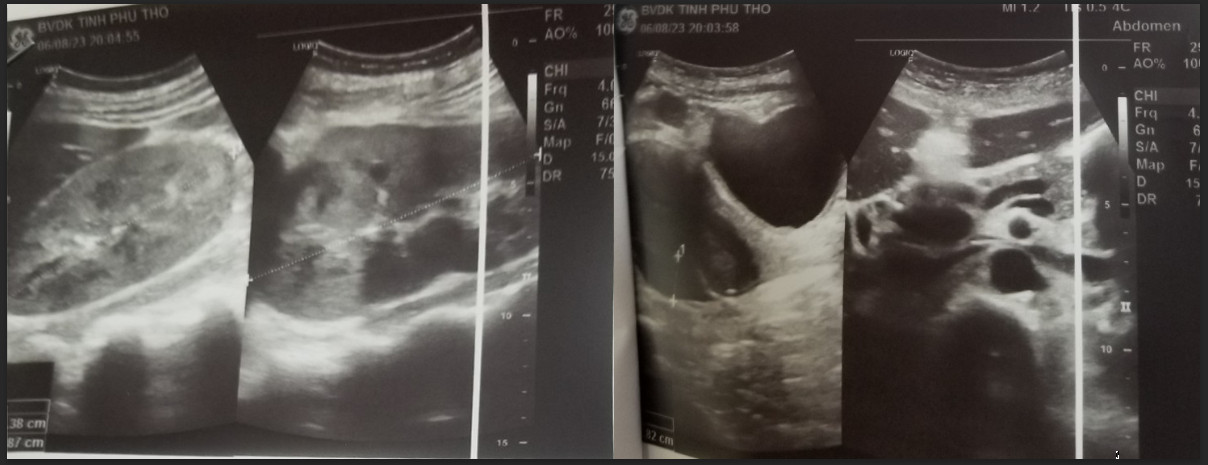

Đi viện vì viêm ruột thừa, người đàn ông vô tình phát hiện bị suy thận

Hương Giang |

Bệnh viện Đa khoa tỉnh Phú Thọ vừa tiếp nhận điều trị người bệnh T.N.Y (38 tuổi) ở Cẩm Khê (Phú Thọ) bị bệnh viêm ruột thừa cấp, trong quá trình thăm khám điều trị phát hiện suy thận, phải kết hợp lọc máu cấp cứu.